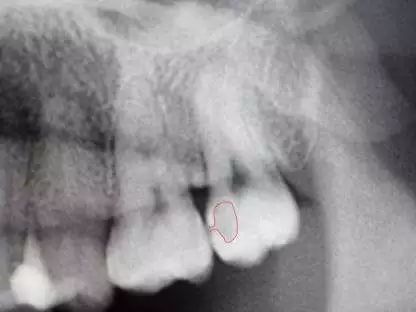

比如,这颗牙齿表面看着好好的,但拍X光片一看,却发现牙齿蛀了。可见,拍X光片是何其重要。

2 根尖片

这种X光片用来观察相邻一颗、两颗或三颗牙齿的整个牙冠和牙根。X光片中也会显示支撑牙齿的骨骼结构。牙医可以通过根尖片,观察乳牙下方的继承恒牙,同时也可以用根尖片找出脓肿,发现牙周疾病。